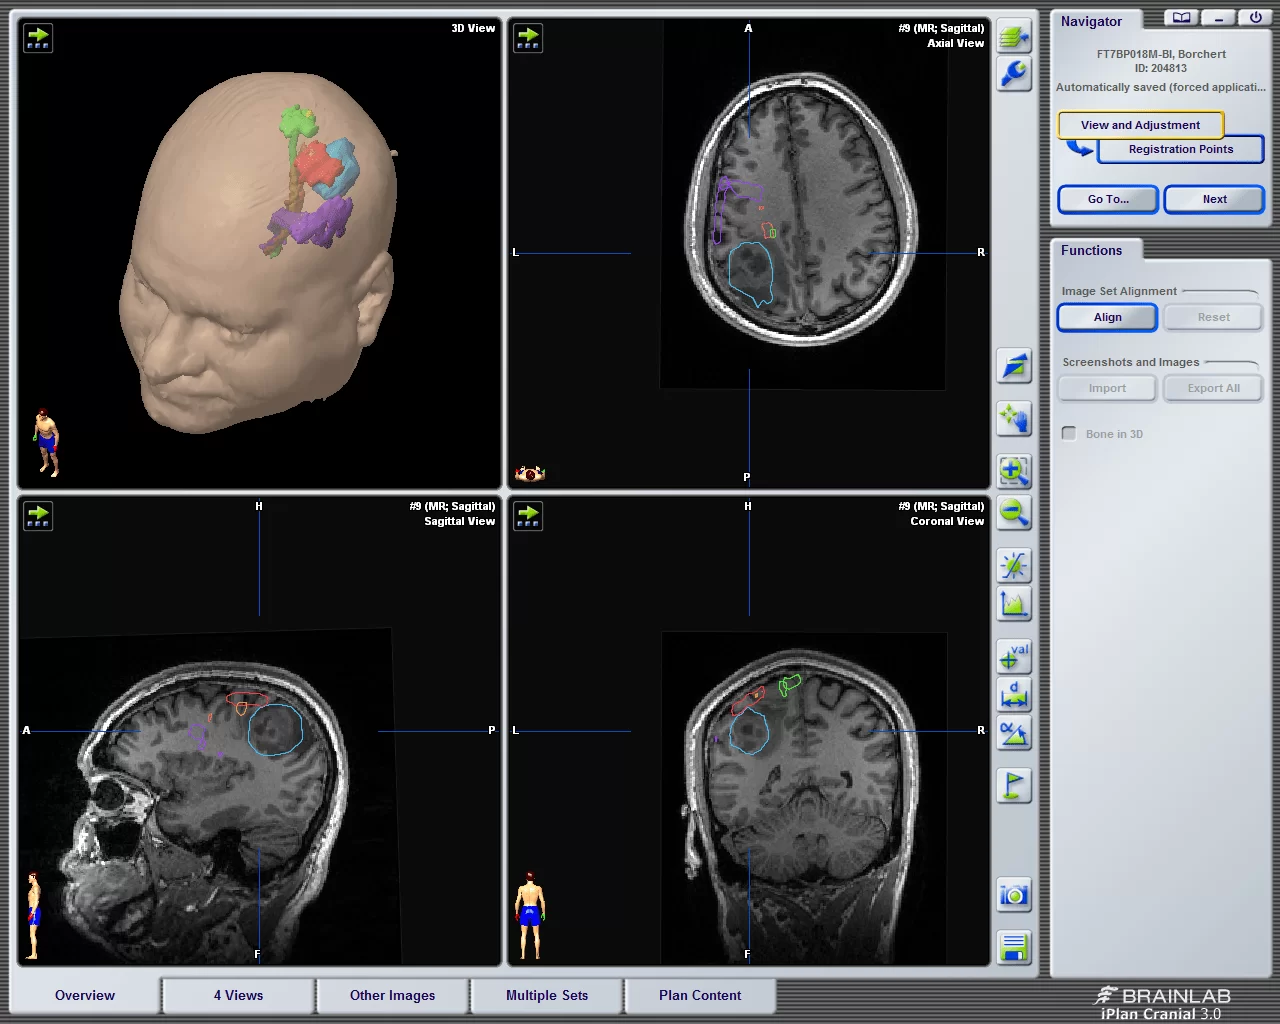

Η βιοψία μπορεί να γίνει σε συνδυασμό με χειρουργική επέμβαση για την αφαίρεση του όγκου. Εναλλακτικά, ένα μικρό δείγμα μπορεί να αφαιρεθεί από τον όγκο με στερεοτακτικές τεχνικές, δηλαδή με την εισαγωγή μιας βελόνας στην ακριβή περιοχή του όγκου, χρησιμοποιώντας νευροπλοήγηση. Γενικά η στερεοτακτική βιοψία είναι ιδιαίτερα ασφαλής μέθοδος, με ποσοστό επιτυχίας περίπου 95%.

Χειρουργική αφαίρεση – Ο στόχος της χειρουργικής επέμβασης είναι η απομάκρυνση όσο το δυνατόν περισσότερου όγκου χωρίς βλάβη στον υγιή εγκέφαλο. Τα δεδομένα της σύγχρονης βιβλιογραφίας δείχνουν ότι η αφαίρεση της βλάβης, ακόμη και αν είναι υφολική (δηλ. αν δεν αφαιρεθεί ολόκληρος ο όγκος), έχει πλεονεκτήματα για την πρόγνωση. Όμως δεν είναι ακόμη σαφές πόσος όγκος πρέπει να αφαιρεθεί προκειμένω ο ασθενής να έχει σημαντικό όφελος από την επέμβαση.

Αυτή η ερώτηση είναι μια απο τις πιο συχνές και επιδέχεται μεγάλης συζήτησης. Η ιατρική και ειδικά η χειρουργική (όπου η παραγωγή ποιοτικών επιστημονικών δεδομένων είναι πιο δύσκολη) είναι επιστήμες όπου στη λήψη των αποφάσεων παίζουν πάρα πολλοί παράγοντες ρόλο και κάθε ασθενής είναι ξεχωριστός και μοναδικός. Για να προσπαθήσω να απαντήσω στην ερώτηση εν συντομία, ο λόγος που συμβαίνει αυτό είναι γιατί κάθε γιατρός εκτιμά την κατάσταση με βάση την εμπειρία του, την εκπαίδευσή του, το χαρακτήρα του και τα μέσα που έχει στη διάθεσή του. Μερικοί όγκοι απαιτούν εκπαίδευση σε πολύ ειδικές προσπελάσεις, ενώ άλλοι όγκοι, όπως για παράδειγμα τα αστροκυττώματα χαμηλής κακοήθειας, μερικές φορές απαιτούν εξειδικευμένες τεχνικές προκειμένω να αφαιρεθούν με ασφάλεια, όπως για παράδειγμα χειρουργείο με τον ασθενή σε εκγρήγορση (awake craniotomy) καθώς επίσης και εκτεταμένο νευροφυσιολογικό έλεγχο. Όλα τα παραπάνω είναι εργαλεία –μερικές φορές απαραίτητα- για την αφαίρεση ενός όγκου. Ο νευροχειρουργός λοιπόν, πρέπει καταρχάς να γνωρίζει τι εργαλεία χρειάζονται και εν συνεχεία να διαθέτει αυτά τα κατάλληλα εργαλεία προκειμένω να διενεργήσει το χειρουργείο σωστά και με ασφάλεια.